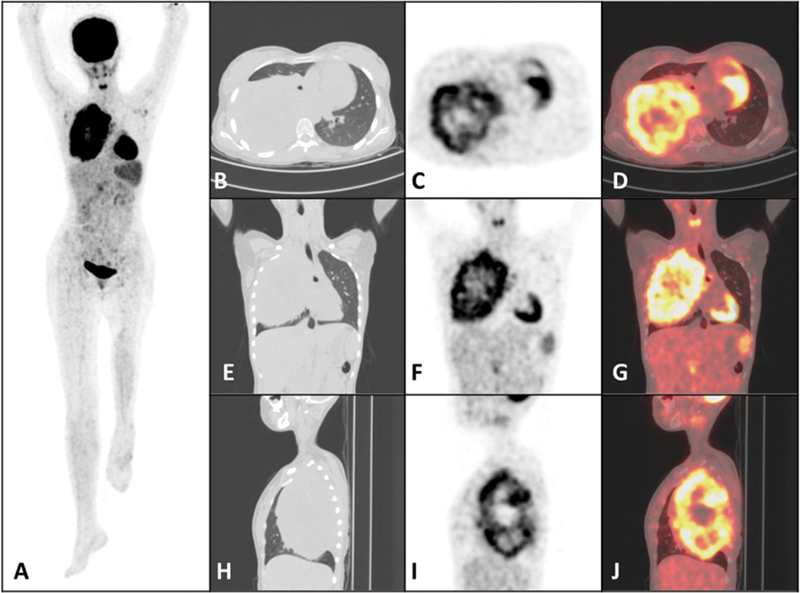

Ewing's sarcoma (ES) is a mesenchymal origin malignant neoplasm that affects children and adolescents. It is the second most common type of bone sarcoma and accounts for approximately 1.5% of all childhood cancers with an annual incidence of 1 to 3 cases per million children under 16 years of age. In this article, we present the case of a 16-year-old adolescent girl. Lung metastasis at the initial diagnosis of ES is relatively uncommon but carries significant prognostic implications. Lung metastases in ES can vary significantly in size, ranging from small nodules (just a few millimeters in size) to the largest reported case being 15 cm. The size of the metastases impacts the choice of therapeutic strategies and the prognosis. Approximately 30% of patients with ES experience a relapse, with the lungs being a common site for metastatic disease. Relapsed lung metastasis on follow-up is a critical concern in the long-term management of ES. We describe a relapsed case of ES in a 16-year-old adolescent girl who presented with a solitary large metastatic right lung mass, with the longest dimension of 16 cm on craniocaudal measurement. The primary site of the tumor was the left distal femur, for which the patient received six cycles of neoadjuvant chemotherapy, followed by en bloc tumor excision and rotationplasty of the left distal femur, after which the patient received seven cycles of adjuvant chemotherapy. Subsequent 5 years of regular follow-up was asymptomatic. Later, the patient presented with back pain and cough, and was diagnosed with a solitary large right lung mass. Computed tomography (CT) guided biopsy of the right lung mass revealed a metastatic ES, for which she underwent chemoradiotherapy. This case highlights the large size of solitary lung metastases in relapsed ES.